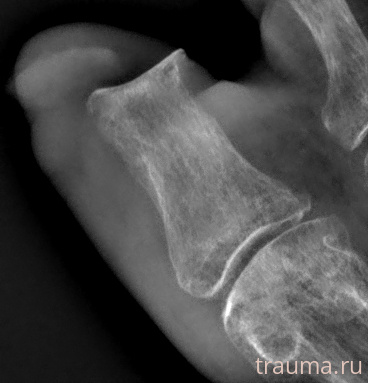

Рентген на дому: по вашему адресу приезжает врач-рентгенолог, травматолог-ортопед с мобильным рентгеновским аппаратом, проводит диагностику травмы или заболевания, делает необходимые рентгенограммы, дает рекомендации по дальнейшему лечению. Получить качественные снимки в домашних условиях возможно благодаря уникальной методике, разработанной МосРентген Центром для института  Склифосовского

при переломе шейки бедра и пневмонии от компании МосРентген Центр - партнера Института имени Склифосовского